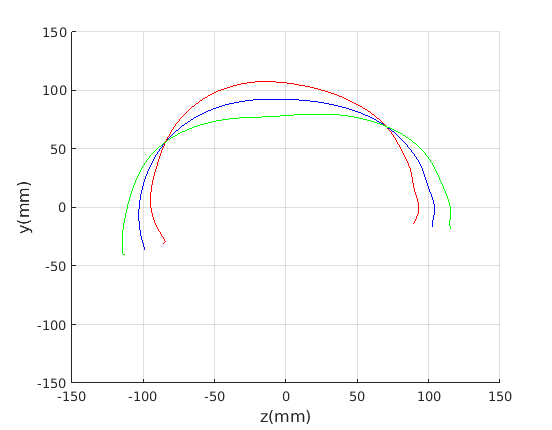

Figure 16 shows examples of the robust ellipse fit for four head profiles. The centre of the ellipse is used in a pose normalisation procedure where the ellipse centre is used as the origin of the profile and the angle from the ellipse centre to the nasion is fixed at -10 degrees. We call this Ellipse Centre - Nasion (ECN) pose normalisation and later compare this to GPA. The major and minor axes of the extracted ellipses are plotted as red and green lines respectively in Fig. 16.

|

Figure 17 shows all 100 profiles overlaid with the same alignment scheme. The median value of major ellipse axis and the ellipse centre-nasion angle differ by 3.6 degrees, so that when the nasion angle is fixed at -10 degrees, the median ellipse angle is -6.4 degrees (cf. -7.4 degrees with manual landmarking of the nasion). We noted regularity in the orientation of the fitted ellipse as is indicated by the clustering of the major (red) and minor (green) axes in Fig. 17 and the histogram of ellipse orientations in Fig. 18. For most people, the major axis of the ellipse is closely aligned with the y-axis (upright), and titled slightly forwards. A minority of heads (9%) in the training sample have their major ellipse axes closer to the vertical (these relatively tall and short heads are known as brachycephalic.) Ellipse axis clustering (relative to the fixed ellipse centre-nasion line) does not appear to be sharply defined. This is because many crania are close to circular in cross-section, making the orientation of these angles sensitive to small changes in shape from one person to the next. Note also the variation at the back of the head due to a variety of hair styles, some of which protrude from under the cap. We limit the region over which we model the cranial shape in order to crop this unwanted data out.